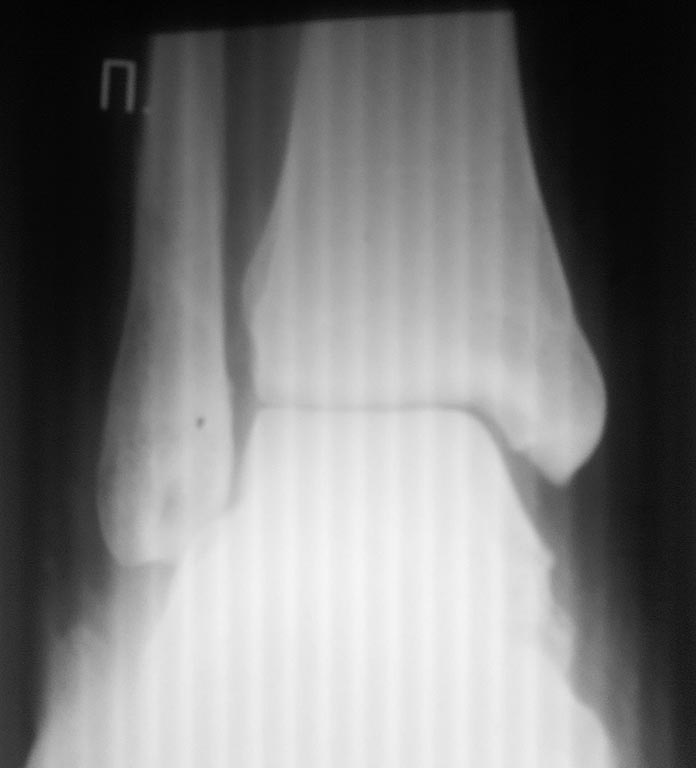

[Ortho] сохраняется подвывих?

пациент отказался. после операции прошло 3 дня, от момента травмы -

неделя. пациент ходит в гипсе без нагрузки на ногу. интересует, что

делать сейчас.

Имя     : 1ДП ПРЕТБГИ?И?1.jpg

Тип     : image/jpeg